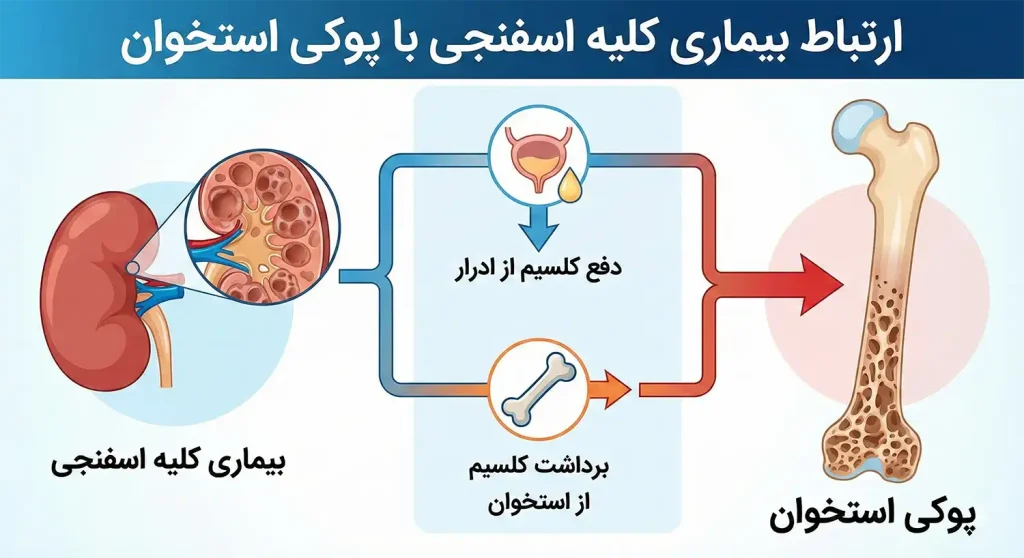

ارتباط بیماری کلیه اسفنجی با پوکی استخوان

یکی از جنبههای بالینی حائز اهمیت در بیماری کلیه اسفنجی، تاثیر مستقیم و غیرمستقیم آن بر سلامت استخوانی بیماران است. مطالعات نشان میدهد که اختلال در بازجذب املاح در لولههای کلیوی میتواند منجر به کاهش تراکم استخوان و در نهایت پوکی استخوان شود.

مکانیسمهای اصلی این ارتباط عبارتند از:

- دفع کلسیم ادراری (Hypercalciuria): کلیه اسفنجی باعث میشود کلیهها نتوانند کلسیم را به درستی بازجذب کنند و مقادیر زیادی کلسیم از طریق ادرار دفع میشود.

- برداشت کلسیم از استخوان: بدن برای حفظ سطح کلسیم خون در محدوده نرمال، مجبور به برداشت کلسیم از منابع ذخیره (استخوانها) میشود که این امر موجب تضعیف بافت استخوانی میگردد.

- اسیدوز توبولار کلیوی (RTA): در برخی موارد، کلیه اسفنجی با نوعی اسیدی شدن خون همراه است که این محیط اسیدی، انحلال مواد معدنی استخوان را تسریع میکند.